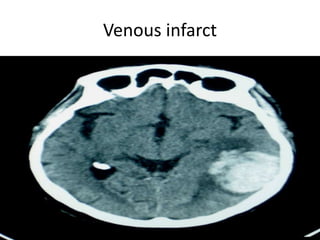

Venous infarct

Vascular Insults • SubarachniodHemorrhage. • Lobar and basal ganglia bleeds. • Ischemic strokes. • Venous infarcts. • Disections